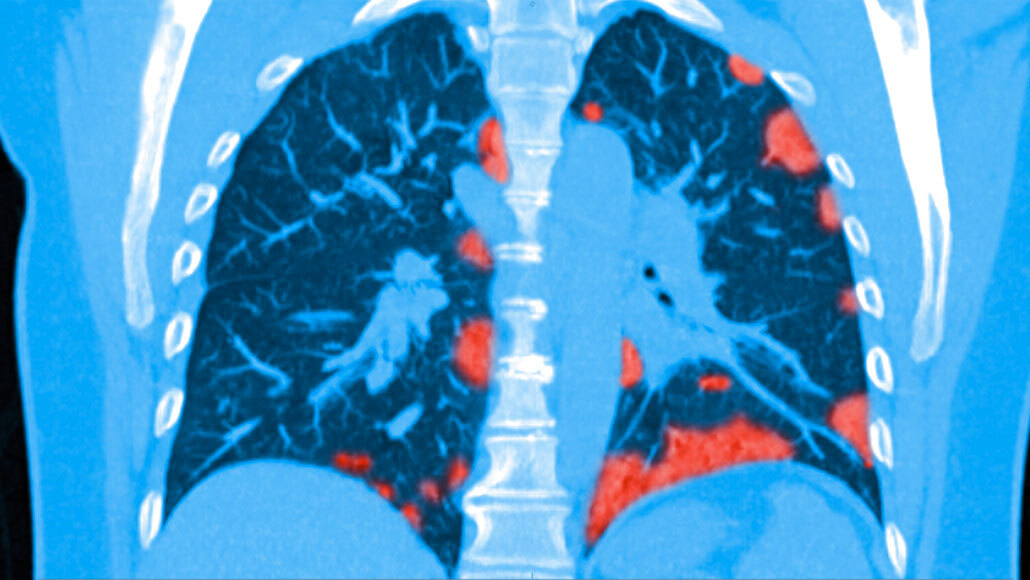

Patchy spots often show up in lung scans of actively sick COVID-19 patients (colorized scan shown). Some lung damage could be long-lasting, new research suggests.

Steven Needell/Science Source